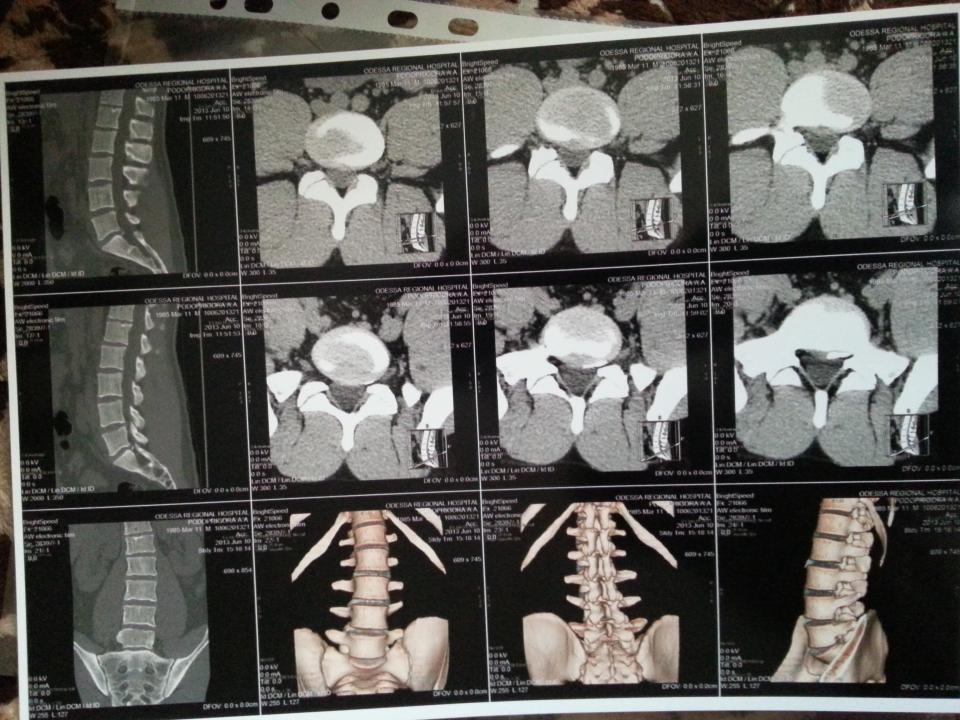

android_69 Опубліковано: 10 червня 2013 Опубліковано: 10 червня 2013 (змінено) вот такое у меня нашли сегодня на кт.что подскажите делать?занимаюсь лифтом Змінено 10 червня 2013 користувачем android_69

yobilovus Опубліковано: 10 червня 2013 Опубліковано: 10 червня 2013 ?занимаюсь лифтом ходи по сходах а що кажуть лікарі? це ж все діагноз, а що з лікуванням? і які в тебе силові в ліфті?